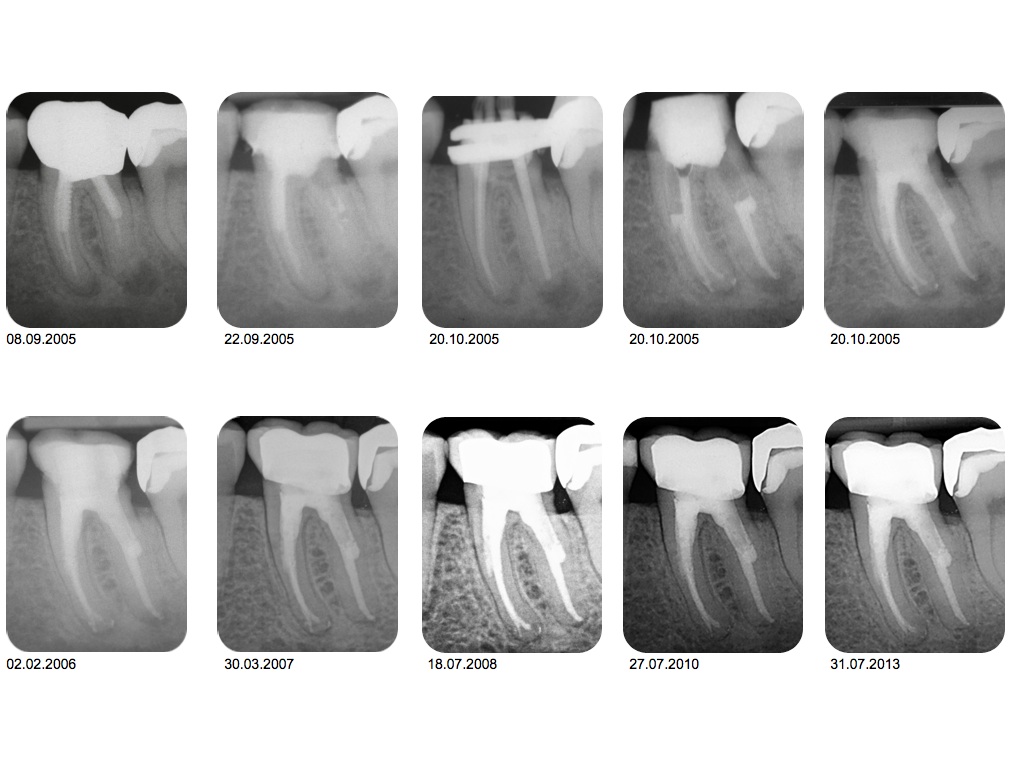

1.001-001